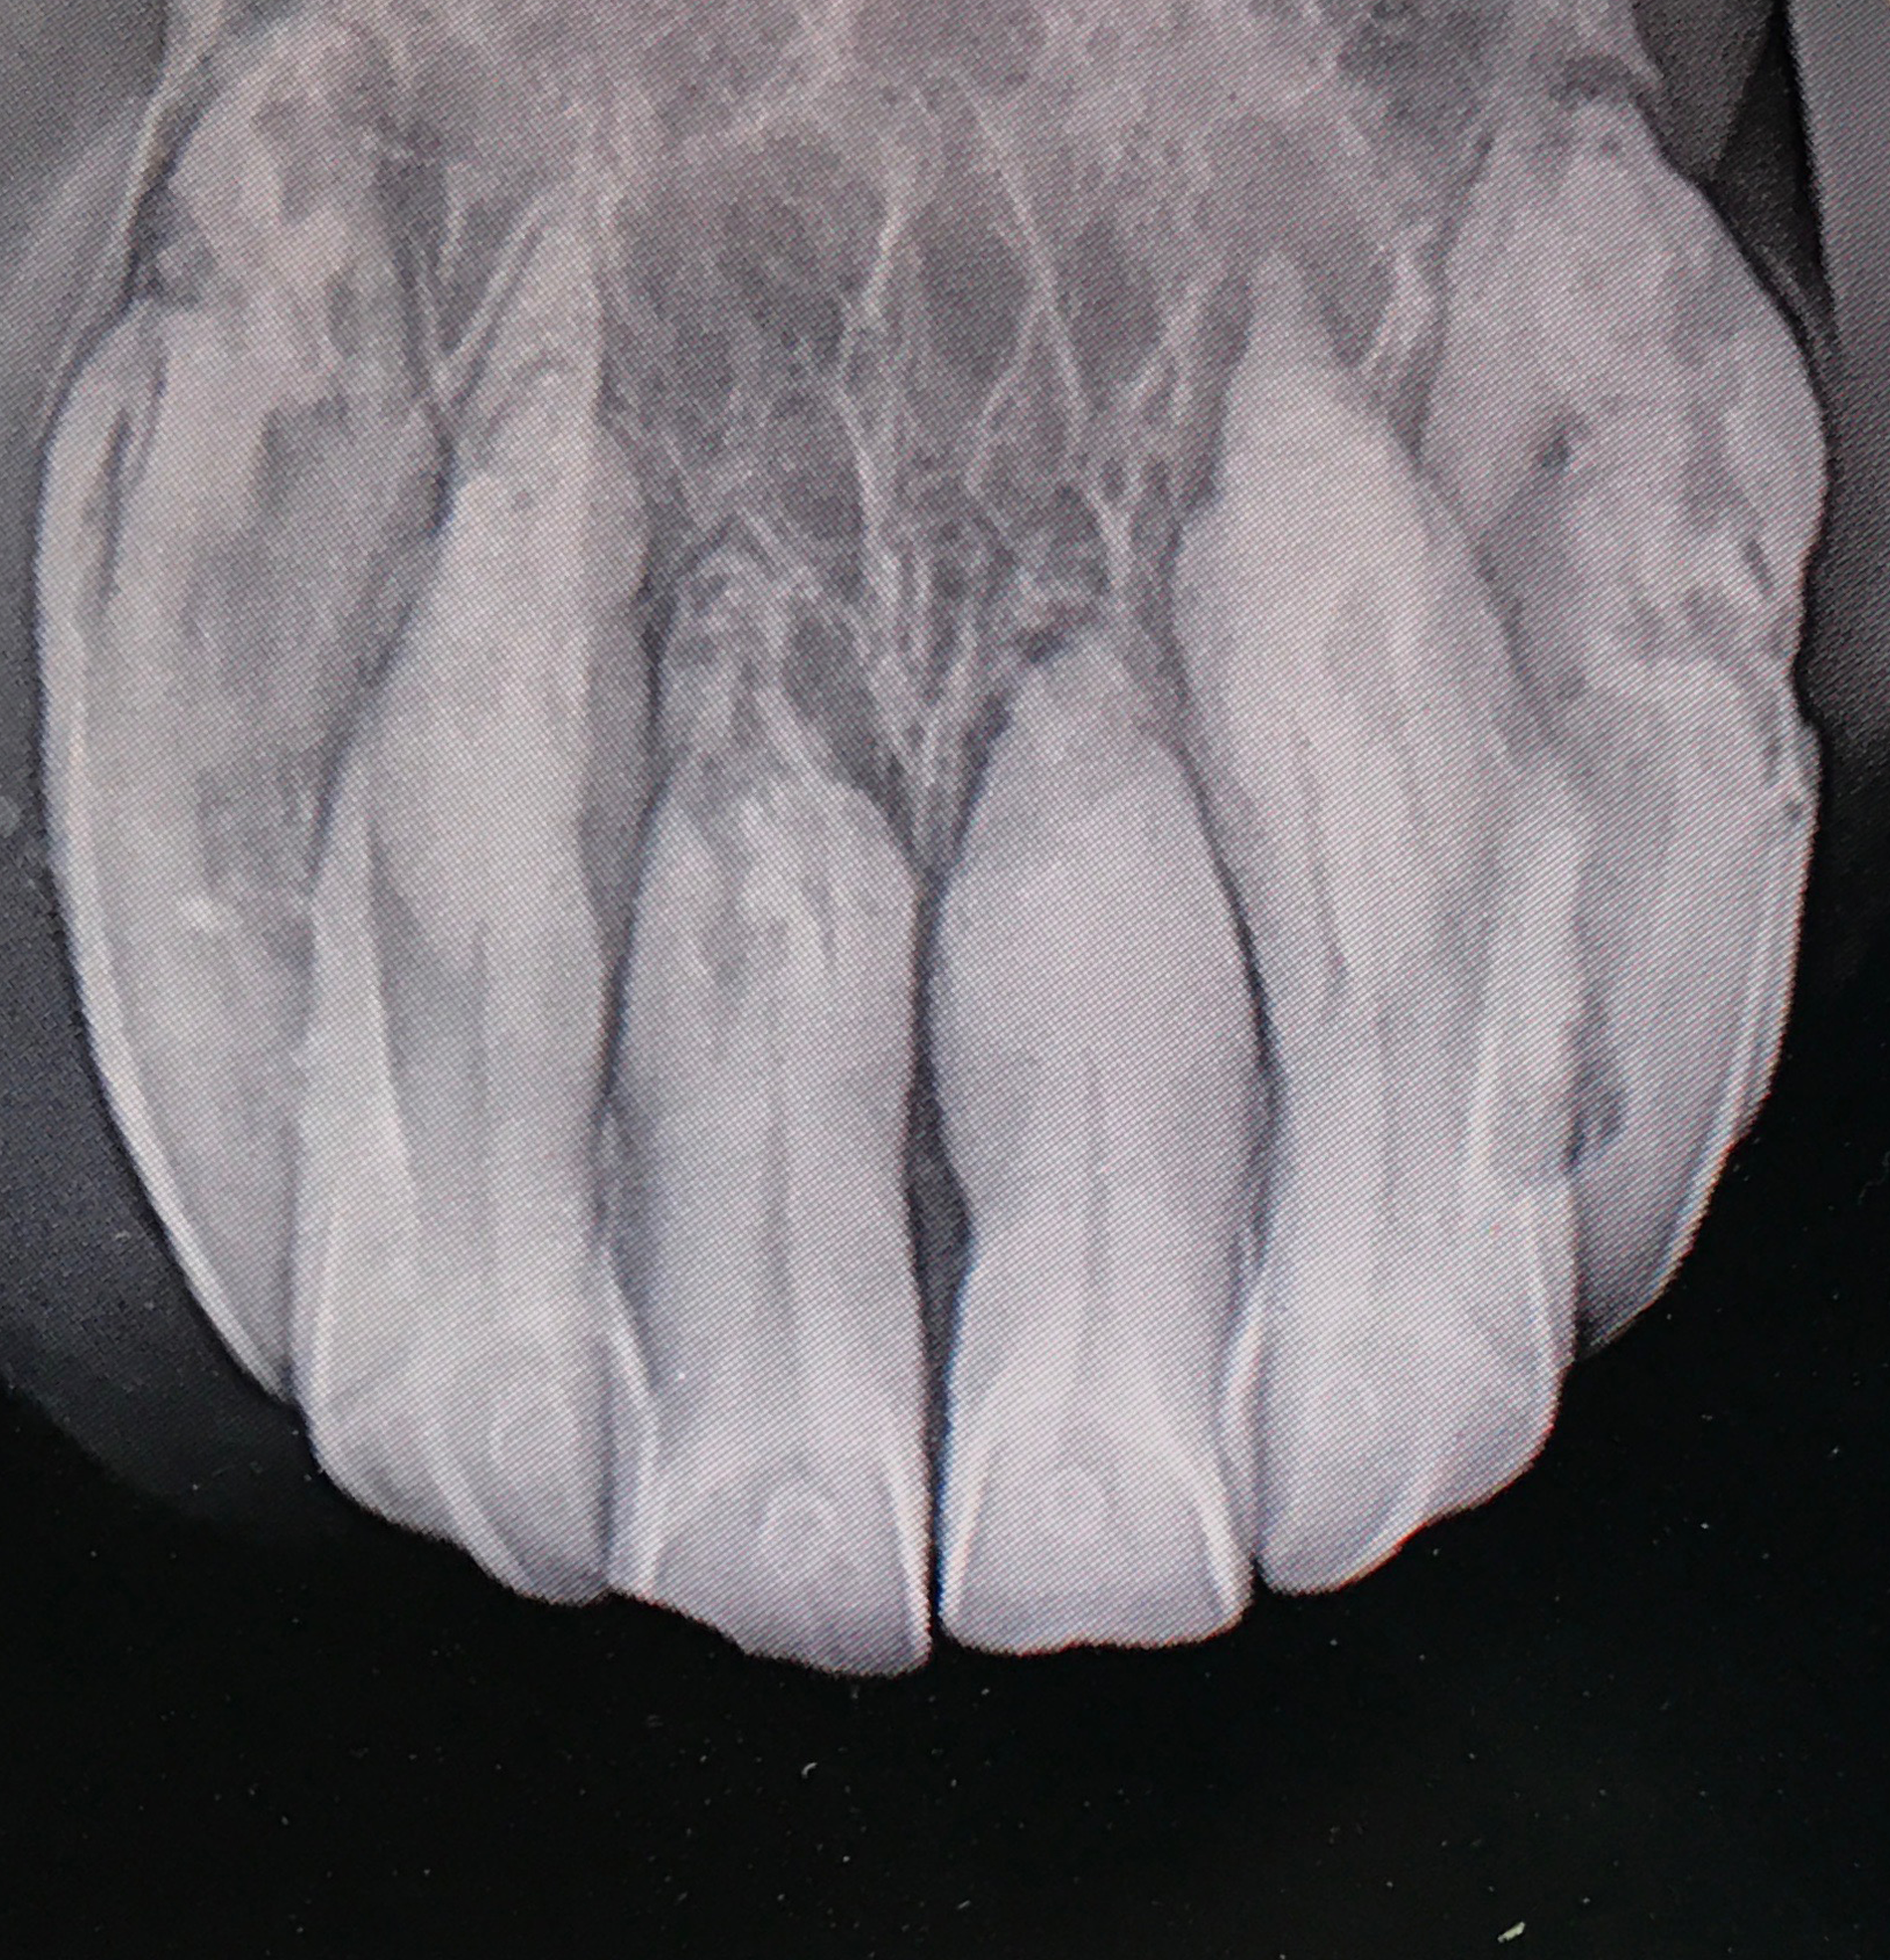

Learn how to radiographically grade EOTRH resorptive lesions and properly assess affected horses.

Do you know how to identify what this is, what to do about it and how to speak to an owner about it?

If the answer is NO then you NEED to be on this masterclass!

Confused about EOTRH? Do you know how to identify this, what to do about it and how to discuss treatment options with your clients?